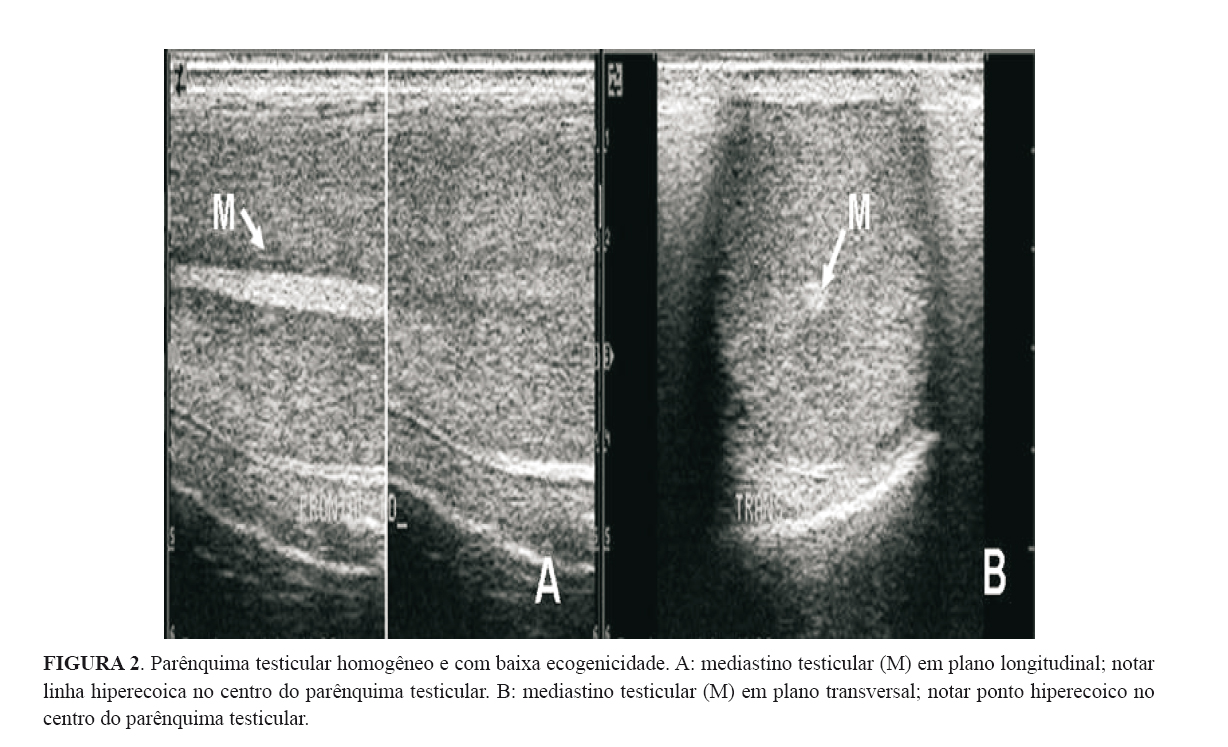

O mediastino testicular, em plano longitudinal, apresentou-se como uma linha hiperecoica no centro do parênquima testicular, com a espessura variando de 1,3 mm a 5 mm (Figura 2A). Em plano transversal foi visualizado como um ponto hiperecoico no centro do parênquima testicular (Figura 2B). Sua identificação tornou-se mais evidente com o avançar da idade, por se tornar a cada momento mais ecogênico.

A espessura média do mediastino testicular aumentou em proporção direta à idade dos animais. Todavia uma diferença significativa (p<0,05) foi detectada somente no intervalo de nove aos treze meses (Tabela 1). A seguinte equação de primeiro grau foi obtida: y= 1,14 + 0,12x  com  R2 = 0,31.

O mediastino testicular, em plano transversal, apresentou-se como um ponto hiperecoico no centro do parênquima testicular; e no plano longitudinal como uma linha hiperecoica variando entre 1,3 mm e 5,0 mm de espessura. Esta estrutura, por ser mais ecogênica, foi mais facilmente identificada nos animais com quinze meses de idade. A espessura do mediastino também aumentou em proporção direta com a idade dos animais. Estas observações contrariam relatos descritos por PECHMAN & EILTS (1987), que ao trabalharem com animais Bos taurus taurus concluíram que a espessura do mediastino e sua ecogenicidade diminuem com a idade. Todavia, assemelham-se às afirmativas de ABDEL-RAZEK & ALI (2005), os quais também avaliaram Bos taurus taurus. Segundo SISSON (1986) e DYCE et al. (1990), os túbulos seminíferos formam no mediastino uma rede, a rede do testículo (rete testis), logo, com o aumento da idade do animal, ocorrem importantes e consideráveis mudanças anatômicas nos túbulos seminíferos, os quais se tornam mais longos e “retorcidos”, aumentam em diâmetro e formam um lúmen (HAMM & FOBBE, 1995), o que pode explicar o aumento da espessura do mediastino testicular.